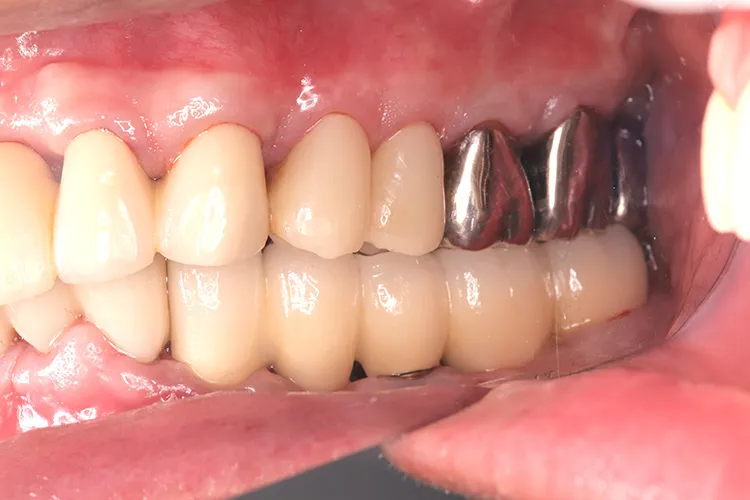

左下5本欠損した部分をインプラント3本埋入して5本ブリッジで治したケースです。なかなかインプラントに踏み切れず、長い間入れ歯を使っておられましたが、噛みごたえがなく好きなものが食べれない上に、度々歯茎が痛んでは調整の繰り返しで快適に過ごすことができず、QOLの向上のためインプラント治療を決断されました。今ではなんでも食べれるとのことで、入れ歯で我慢しないでもっと早くインプラントにすればよかったと言っておられます。